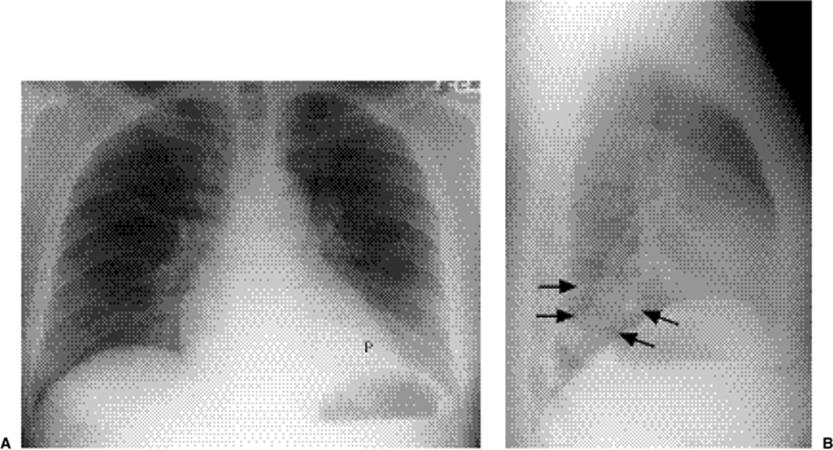

Focal opacity may be visible, especially when comparing one lung with the other on the frontal projection. On the lateral projection attention should be directed over the thoracic spine, the cardiac silhouette, and the retrosternal and retrocardiac regions, where faint opacity may otherwise escape detection (Figs. 5.1 and 5.2).

Figure 5.2 Opacity in pneumonia. (A) Posteroanterior and (B) lateral chest radiographs: vague retrocardiac abnormality (P) with corresponding increased opacity over the lower thoracic spine on the lateral view (arrows).